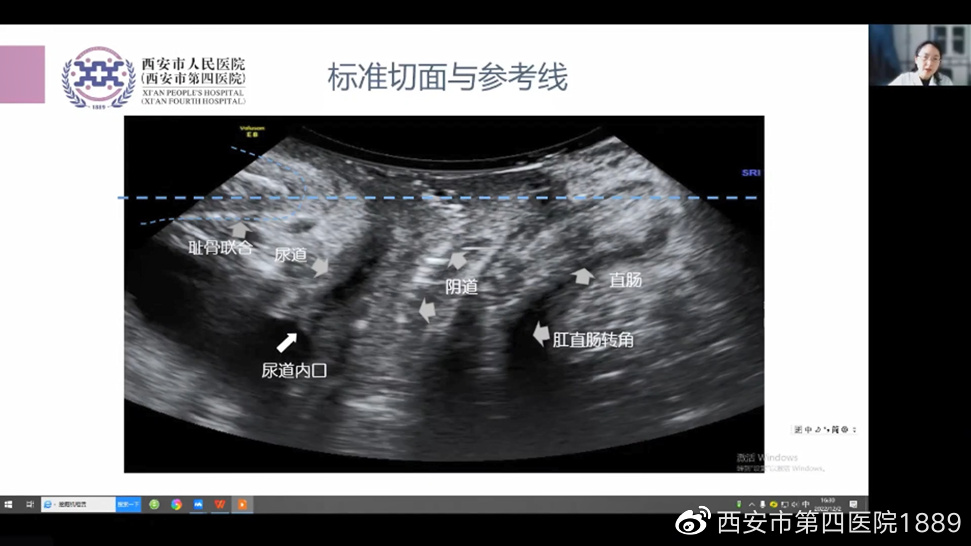

产后康复技术的发展与应用专场,特邀产后康复/盆底康复中心李丹副主任、范祎主任医师、黄文成教授、沈经国教授、欧洲生物反馈协会(BFE)讲师齐勤、张慧副主任、妇保中心王晓蕾医师,分别围绕产后盆底痛特点及临床诊疗思路、疼痛图谱的解读及临床应用、骨盆评估与矫正手法的应用、整脊在产后医学中的应用、“磁电联合”在产后的应用及进展、超声在盆底康复中的应用、营养与体重管理在产后康复中的应用等内容,进行了应用探讨。